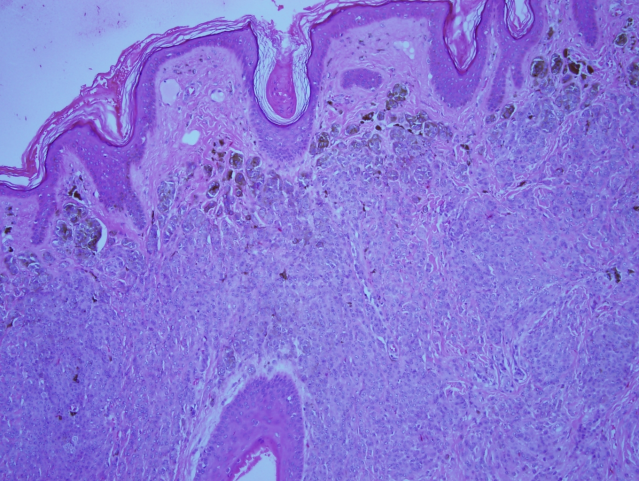

All the specimens collected were sent to the histopathology lab and the report revealed that the specimens had nests and diffusely cellular sheets of benign melanocyte with superficial focal pigmentation and deep dermal maturation. Lateral margins and deeper margins were involved. Overall, there was no malignancy reported (Figure 8 [Fig. 8], Figure 9 [Fig. 9]).

Figure 8: Higher power shows dermal nests with marked adnexocentricity, in addition to infiltrating between the collagen bundles.